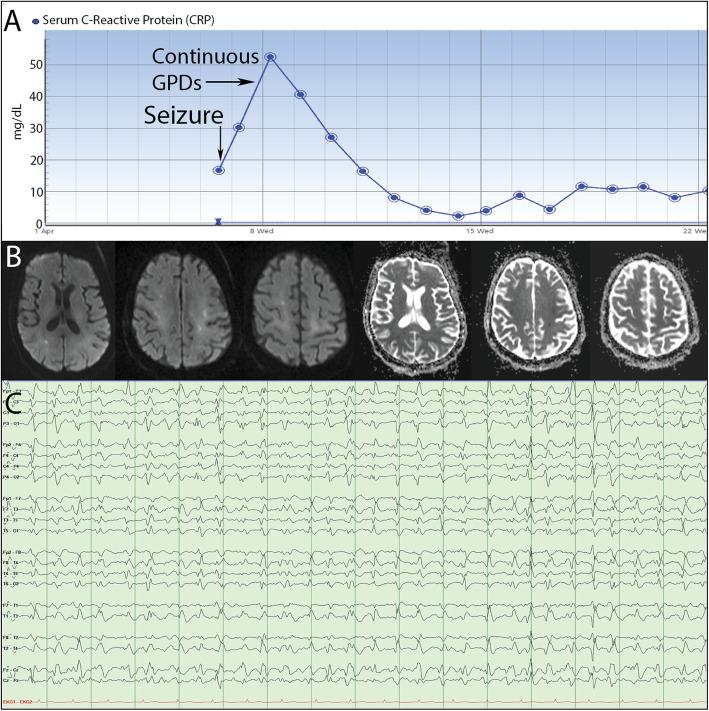

Coronavirus disease 2019 (COVID-19) is a highly infectious pandemic caused by a novel coronavirus called severe acute respiratory syndrome coronavirus 2 (SARS-CoV-2). It frequently presents with unremitting fever, hypoxemic respiratory failure, and systemic complications (e.g., gastrointestinal, renal, cardiac, and hepatic involvement), encephalopathy, and thrombotic events. The respiratory symptoms are similar to those accompanying other genetically related beta-coronaviruses (CoVs) such as severe acute respiratory syndrome CoV (SARS-CoV) and Middle East Respiratory Syndrome CoV (MERS-CoV). Hypoxemic respiratory symptoms can rapidly progress to Acute Respiratory Distress Syndrome (ARDS) and secondary hemophagocytic lymphohistiocytosis, leading to multi-organ system dysfunction syndrome. Severe cases are typically associated with aberrant and excessive inflammatory responses. These include significant systemic upregulation of cytokines, chemokines, and pro-inflammatory mediators, associated with increased acute-phase proteins (APPs) production such as hyperferritinemia and elevated C-reactive protein (CRP), as well as lymphocytopenia. The neurological complications of SARS-CoV-2 infection are high among those with severe and critical illnesses. This review highlights the central nervous system (CNS) complications associated with COVID-19 attributed to primary CNS involvement due to rare direct neuroinvasion and more commonly secondary CNS sequelae due to exuberant systemic innate-mediated hyper-inflammation. It also provides a theoretical integration of clinical and experimental data to elucidate the pathogenesis of these disorders. Specifically, how systemic hyper-inflammation provoked by maladaptive innate immunity may impair neurovascular endothelial function, disrupt BBB, activate CNS innate immune signaling pathways, and induce para-infectious autoimmunity, potentially contributing to the CNS complications associated with SARS-CoV-2 infection. Direct viral infection of the brain parenchyma causing encephalitis, possibly with concurrent neurovascular endotheliitis and CNS renin angiotensin system (RAS) dysregulation, is also reviewed.